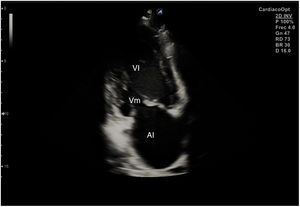

En la ecocardiografía se utilizan sondas sectoriales de baja frecuencia (2 a 5MHz), parecidas a las convex pero con una superficie de contacto con la piel mucho más pequeña, lo que permite evitar la sombra acústica que producen las costillas y mejorar la visión (fig. 1).

El plano paraesternal de eje largo se obtiene con la sonda sobre el segundo o el tercer espacio intercostal izquierdo, próxima al esternón y perpendicular a la piel, sobre una línea que une el hombro derecho con la cadera izquierda (fig. 2). La zona más próxima al transductor es la pared anterior del ventrículo derecho (VD), siendo también visibles la válvula mitral, la válvula aórtica (valva coronaria derecha y no coronaria), el ventrículo izquierdo (VI), la aurícula izquierda (AI), el tracto de salida del VI con la raíz aórtica, parte de la aorta ascendente y el pericardio. Si el corte es bueno, el septo interventricular anterior y la pared anterior de la aorta deben estar alineadas al mismo nivel y dispuestas de forma perpendicular al plano de estudio. La válvula mitral aparece en el centro de la imagen, de forma que su valva anterior se continúa con la pared posterior de la aorta. La aorta descendente puede verse también por detrás de la AI (fig. 3).